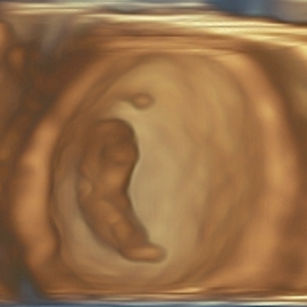

9 Weeks Pregnant

Size: ~0.9 inch (2.3 cm), the size of a Grape!

Development Highlights:

Limbs grow longer; elbows and knees visible.

Tooth buds appear under gums.

Eyes more developed, but eyelids remain fused.

Brain continues rapid development; nervous system forming connections.